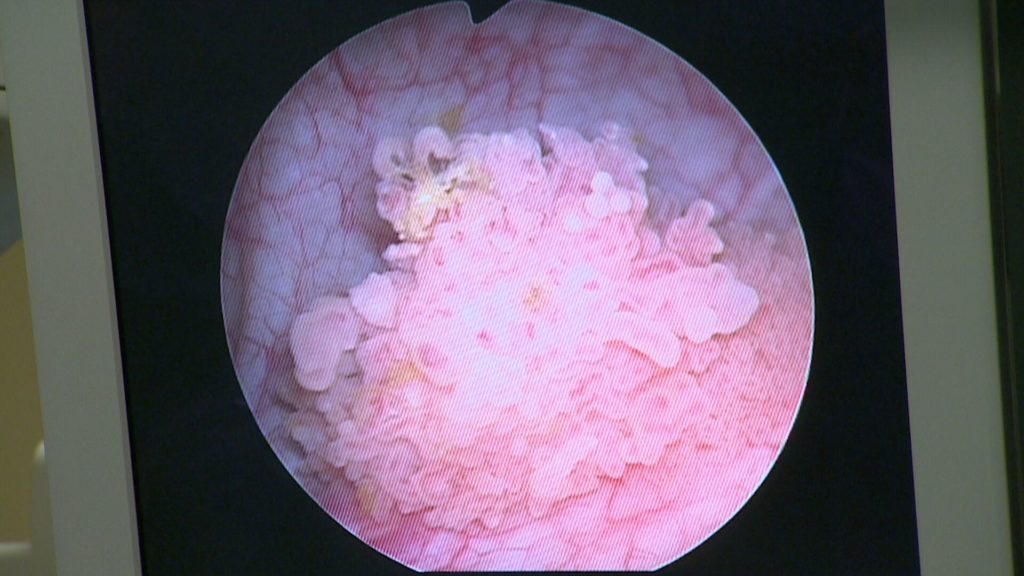

Sendungen 2018 Blasenkrebs–Alarm: Blut im Urin Sendung vom 17. März 2018 Dass Rauchen der Lunge schadet, ist bekannt. Aber nur Wenige…admin17. März 2018